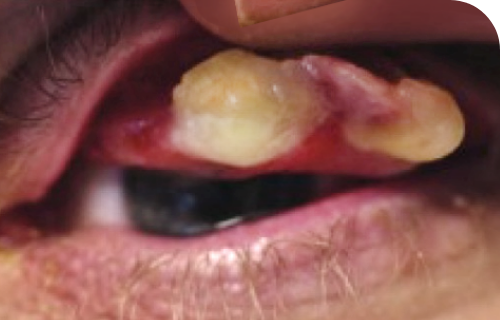

Ligneous conjunctivitis with lesion similar in appearance to conjunctival papilloma

Ligneous conjunctivitis in a real patient with PLGD-14

87% of people with PLGD-1 have ligneous conjunctivitis (LC)6†

The earliest signs of ligneous conjunctivitis typically resemble other common ocular conditions like pink eye or pyogenic granulomas, but if left untreated can lead to vision loss or blindness.5

Ligneous conjunctivitis is a rare, chronic, and recurrent form of pseudomembranous conjunctivitis characterized by the formation of fibrinous pseudomembranes on the palpebral conjunctivae.10

Signs of LC include mucoid discharge, chronic tearing, and redness of the conjunctivae, often resembling other ocular conditions like bacterial conjunctivitis, pyogenic granuloma, conjunctival papilloma, or inclusion cysts.5,10

Symptoms may progress to the formation of pseudomembranes on the palpebral conjunctivae, eventually leading to mucosal thickening with a wood-like (ligneous) consistency that replaces the normal eyelid mucosa.1

Pseudomembranous conjunctivitis caused by plasminogen deficiency type 1, with a watery and stringy appearance Ligneous conjunctivitis manifesting as watery, red eyes with lesions in lower eyelid

Ligneous conjunctivitis caused by congenital plasminogen deficiency type 1, manifesting as an eye lesion, prior to treatment with RYPLAZIM Ligneous conjunctivitis with lesion similar in appearance to conjunctival papilloma

Differing severities of ligneous conjunctivitis in real PLGD-1 patients4